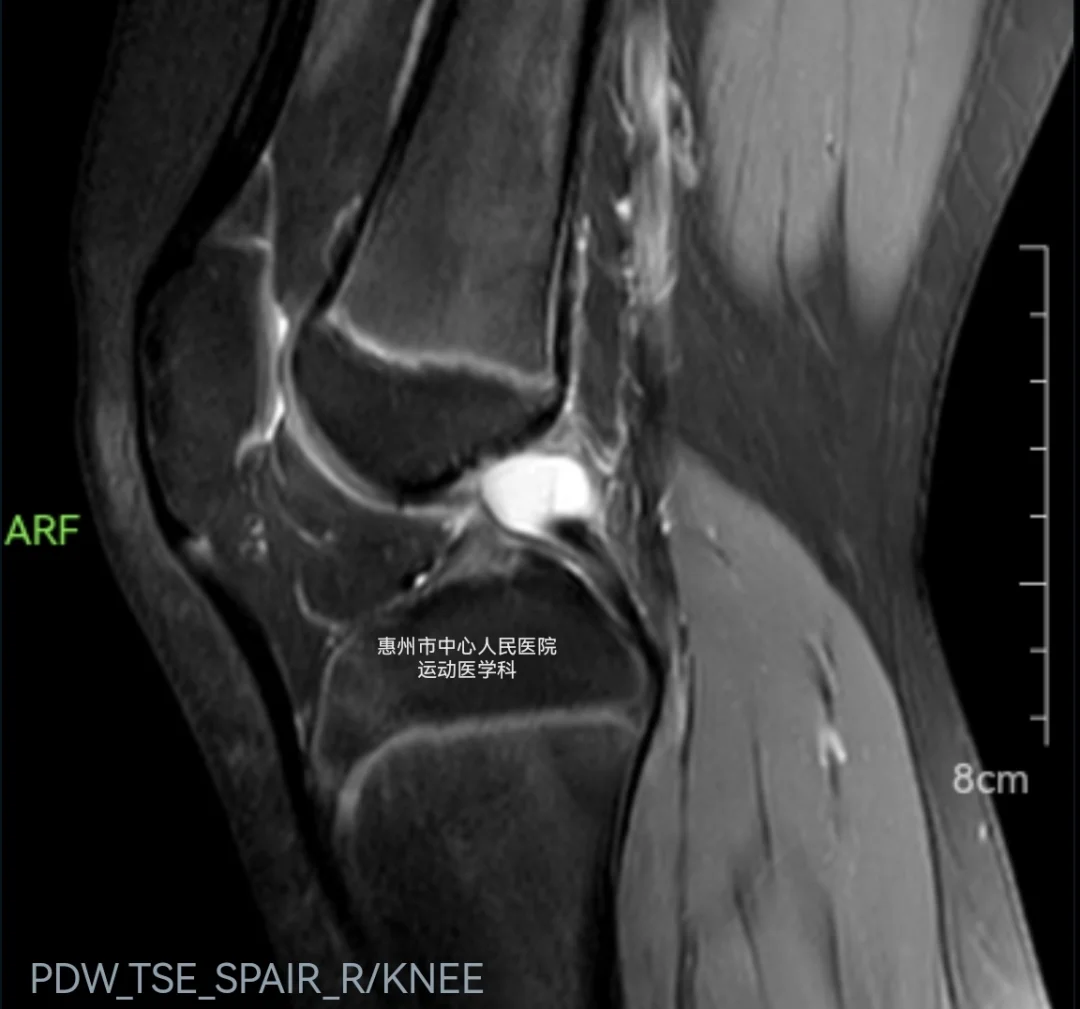

看了一下片子,后交叉韧带有个高亮的囊性组织,应该是后交叉韧带囊肿,通俗地说就是后交叉韧带长了个“水泡”,里面通常包裹的是淡黄色的囊液或者果冻样内容物。